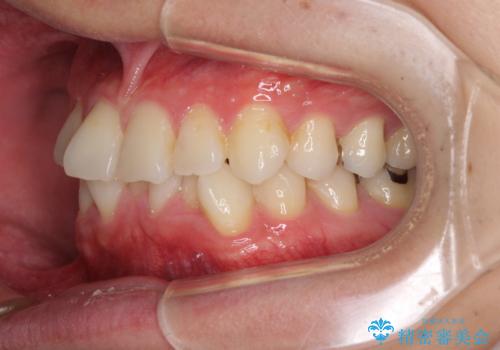

- 右下奥歯の虫歯がしみて痛いとのことで来院された患者様です。

神経近くにまで及ぶ大きな虫歯でしたが、速やかに処置を行い、痛みは即日解消されました。

虫歯が大きかったため、クラウンによる補綴治療が必要になる旨をお伝えしたところ、矯正治療にも興味があるとのことでした。

短期間で手間のかからない方法がご希望でしたので、ワイヤー装置による矯正治療を行うこととし、矯正治療後に右奥2歯をセラミッククラウンにて補綴することとしました。